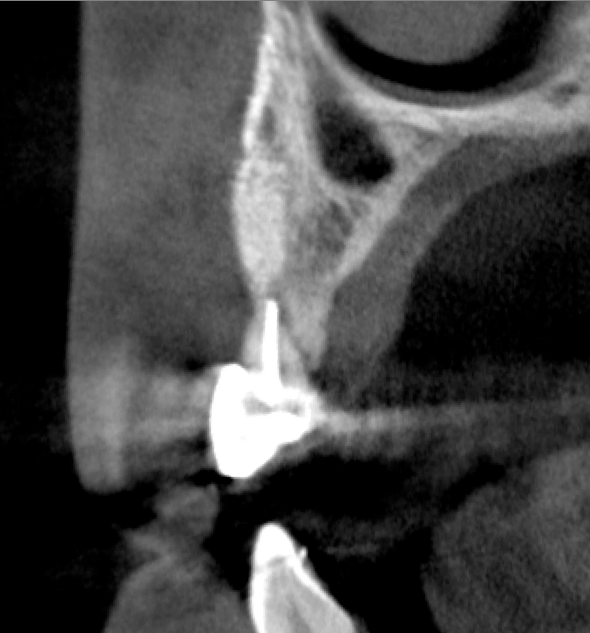

Tomographic images revealed a large tridimensional defect, with vertical and horizontal loss of bone extending to the apical third of teeth Nos. 6 and 8. Additionally, a buccal bone dehiscence was evident on tooth No. 5, and thin labial plates secondary to the orthodontic movement were present in several areas (Figure 3 and Figure 4).

Fig 3. Tomographic images revealed a tridimensional defect extending to the apical third of teeth Nos. 6 and 8, a buccal bone dehiscence on tooth No. 5, and associated thin labial plates.

Figure 3

Fig 4. Tomographic images revealed a tridimensional defect extending to the apical third of teeth Nos. 6 and 8, a buccal bone dehiscence on tooth No. 5, and associated thin labial plates.

Figure 4

Fig 10. Tomographic images of teeth Nos. 6 (Fig 10), 7 (Fig 11), and 8 (Fig 12) clearly showed vertical gains in alveolar height, including in the edentulous area corresponding to tooth No. 7. The apex of tooth No. 8 was located within the soft tissue because it was force-erupted beyond its socket.

Figure 10

Fig 11. Tomographic images of teeth Nos. 6 (Fig 10), 7 (Fig 11), and 8 (Fig 12) clearly showed vertical gains in alveolar height, including in the edentulous area corresponding to tooth No. 7. The apex of tooth No. 8 was located within the soft tissue because it was force-erupted beyond its socket.

Figure 11

Fig 12. Tomographic images of teeth Nos. 6 (Fig 10), 7 (Fig 11), and 8 (Fig 12) clearly showed vertical gains in alveolar height, including in the edentulous area corresponding to tooth No. 7. The apex of tooth No. 8 was located within the soft tissue because it was force-erupted beyond its socket.

Figure 12

After 3 months of post-orthodontic stabilization, a cone-beam computed tomography scan was taken to re-evaluate the results and plan the future treatment sequence. Tomographic images clearly showed vertical gains in alveolar height, including in the edentulous area corresponding to tooth No. 7 (Figure 10 through Figure 12). The apex of tooth No. 8 was forced-erupted beyond its socket and could be visibly located within the soft tissue.30,33